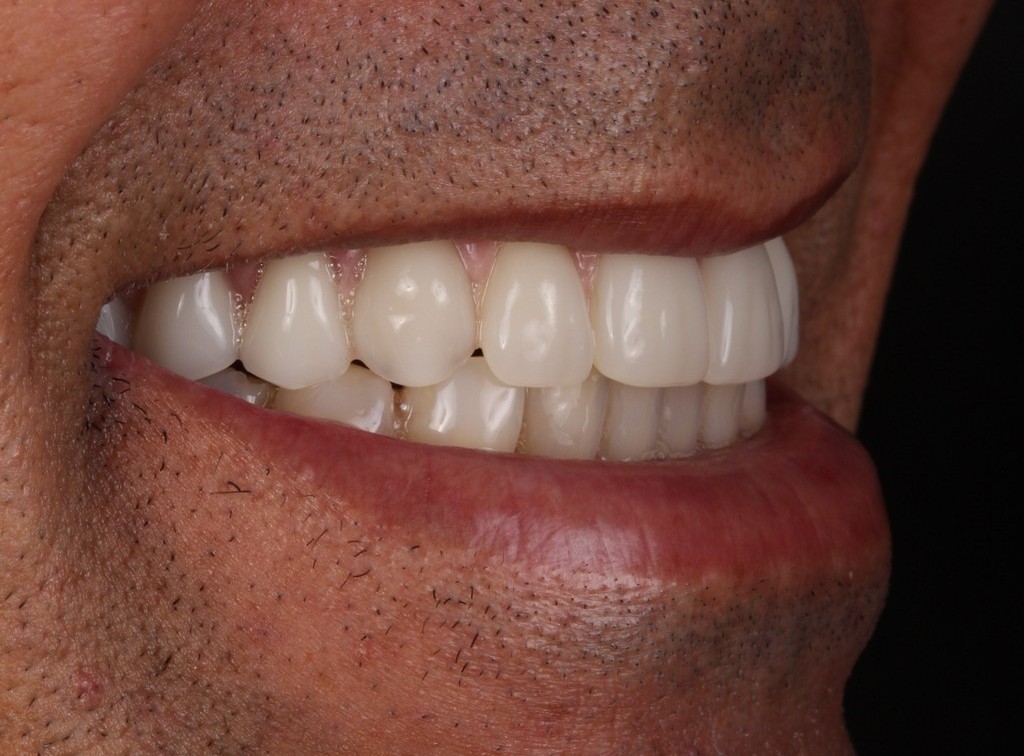

PRÓTESE TOTAL FIXA EM IMPLANTES

C.B.D.S.